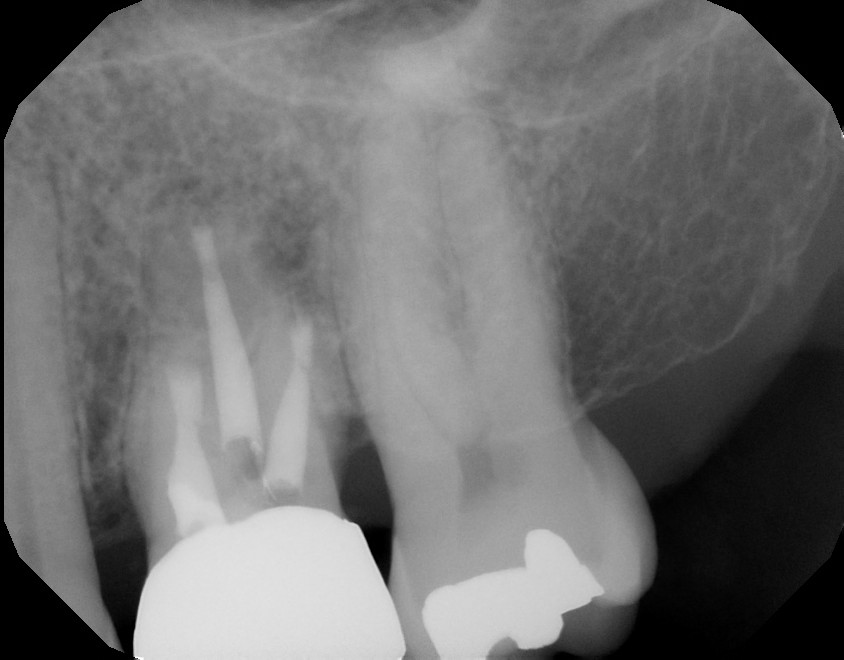

Surgical PreOp

Endodontic surgery on maxillary molars is usually limited to the MB and DB roots - through a buccal approach. Surgical treatment of the palatal root often requires a palatal surgical approach, and is therefore rarely done.  In this particular surgical case, due to the root anatomy and size of the periapical lesion and osteotomy, all three roots were accessed through a buccal surgical approach.